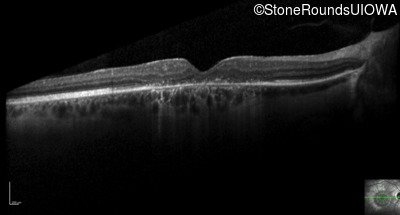

Optical Coherence Tomography - Right - 20/60 sc

Exemplar / OCT Stack